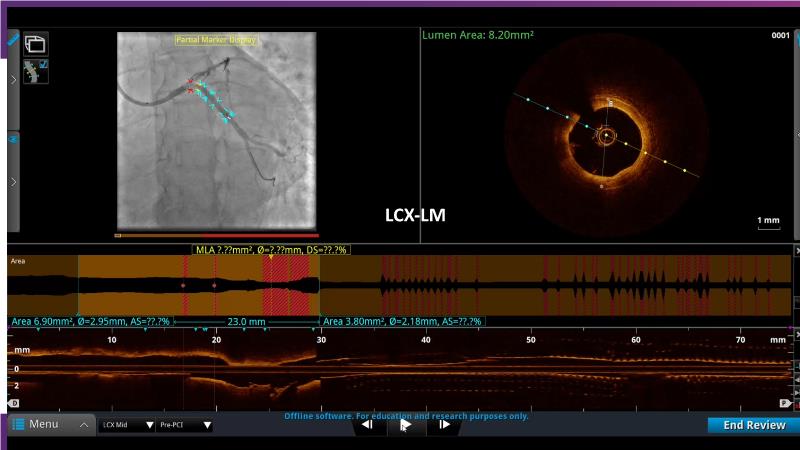

- To define the use of OCT in PCI of complex coronary lesions